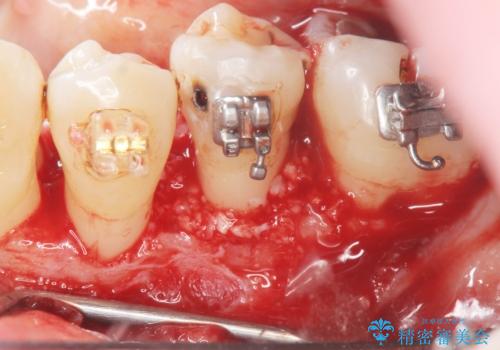

歯周病再生治療と歯周ポケット除去 歯周外科手術

重度の歯周病で再生療法の適応ではない最後方臼歯は抜去行い、インプラント治療、

がたつきの強い天然歯を矯正治療で整えたのち、再生治療、歯周ポケットを除去する歯周外科手術を行いました。

再生療法を行ったことで、抜歯をされてもおかしくなかった歯を、残すことができました。